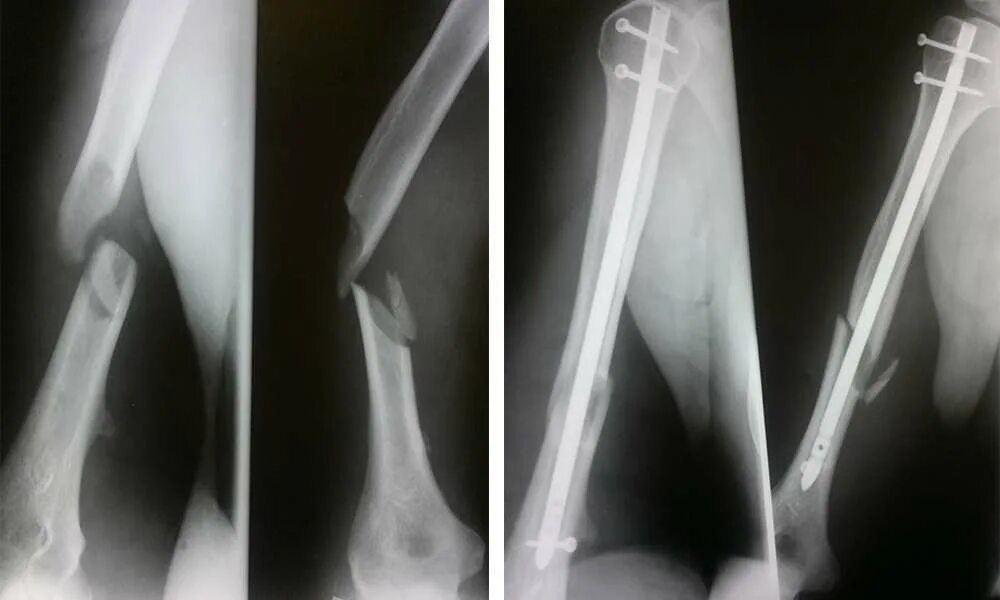

Заросший перелом со смещением